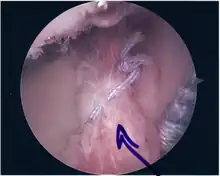

Procedure

Following inspection and determination of the extent of injury, the basic labrum repair is as follows.

- The glenoid and labrum are roughened to increase contact surface area and promote re-growth.

- Locations for the bone anchors are selected based on number and severity of tear. A severe tear involving both SLAP and Bankart lesions may require seven anchors. Simple tears may only require one.

- The glenoid is drilled for the anchor implantation.

- Anchors are inserted in the glenoid.

- The suture component of the implant is tied through the labrum and knotted such that the labrum is in tight contact with the glenoid surface.